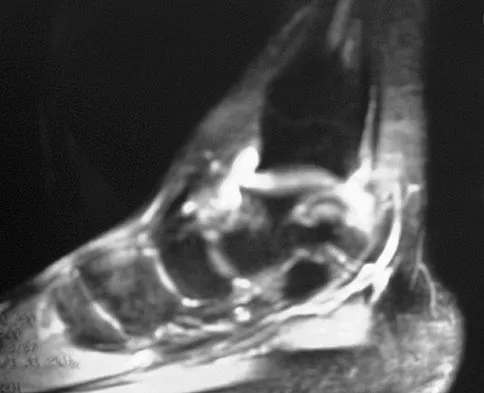

Figure 7 shows the MRI scan of a 23-year-old competitive rugby player who has anterior ankle pain and swelling. He states that he has been playing for many years and has sprained his ankle several times. Examination will reveal what specific hallmark feature?

Detailed Explanation